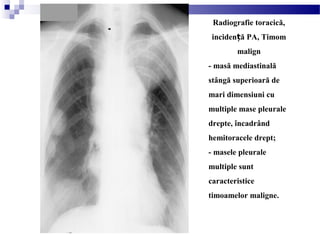

Radiografie toracică,

inciden ă PA, Timomț

malign

- masă mediastinală

stângă superioară de

mari dimensiuni cu

multiple mase pleurale

drepte, încadrând

hemitoracele drept;

- masele pleurale

multiple sunt

caracteristice

timoamelor maligne.